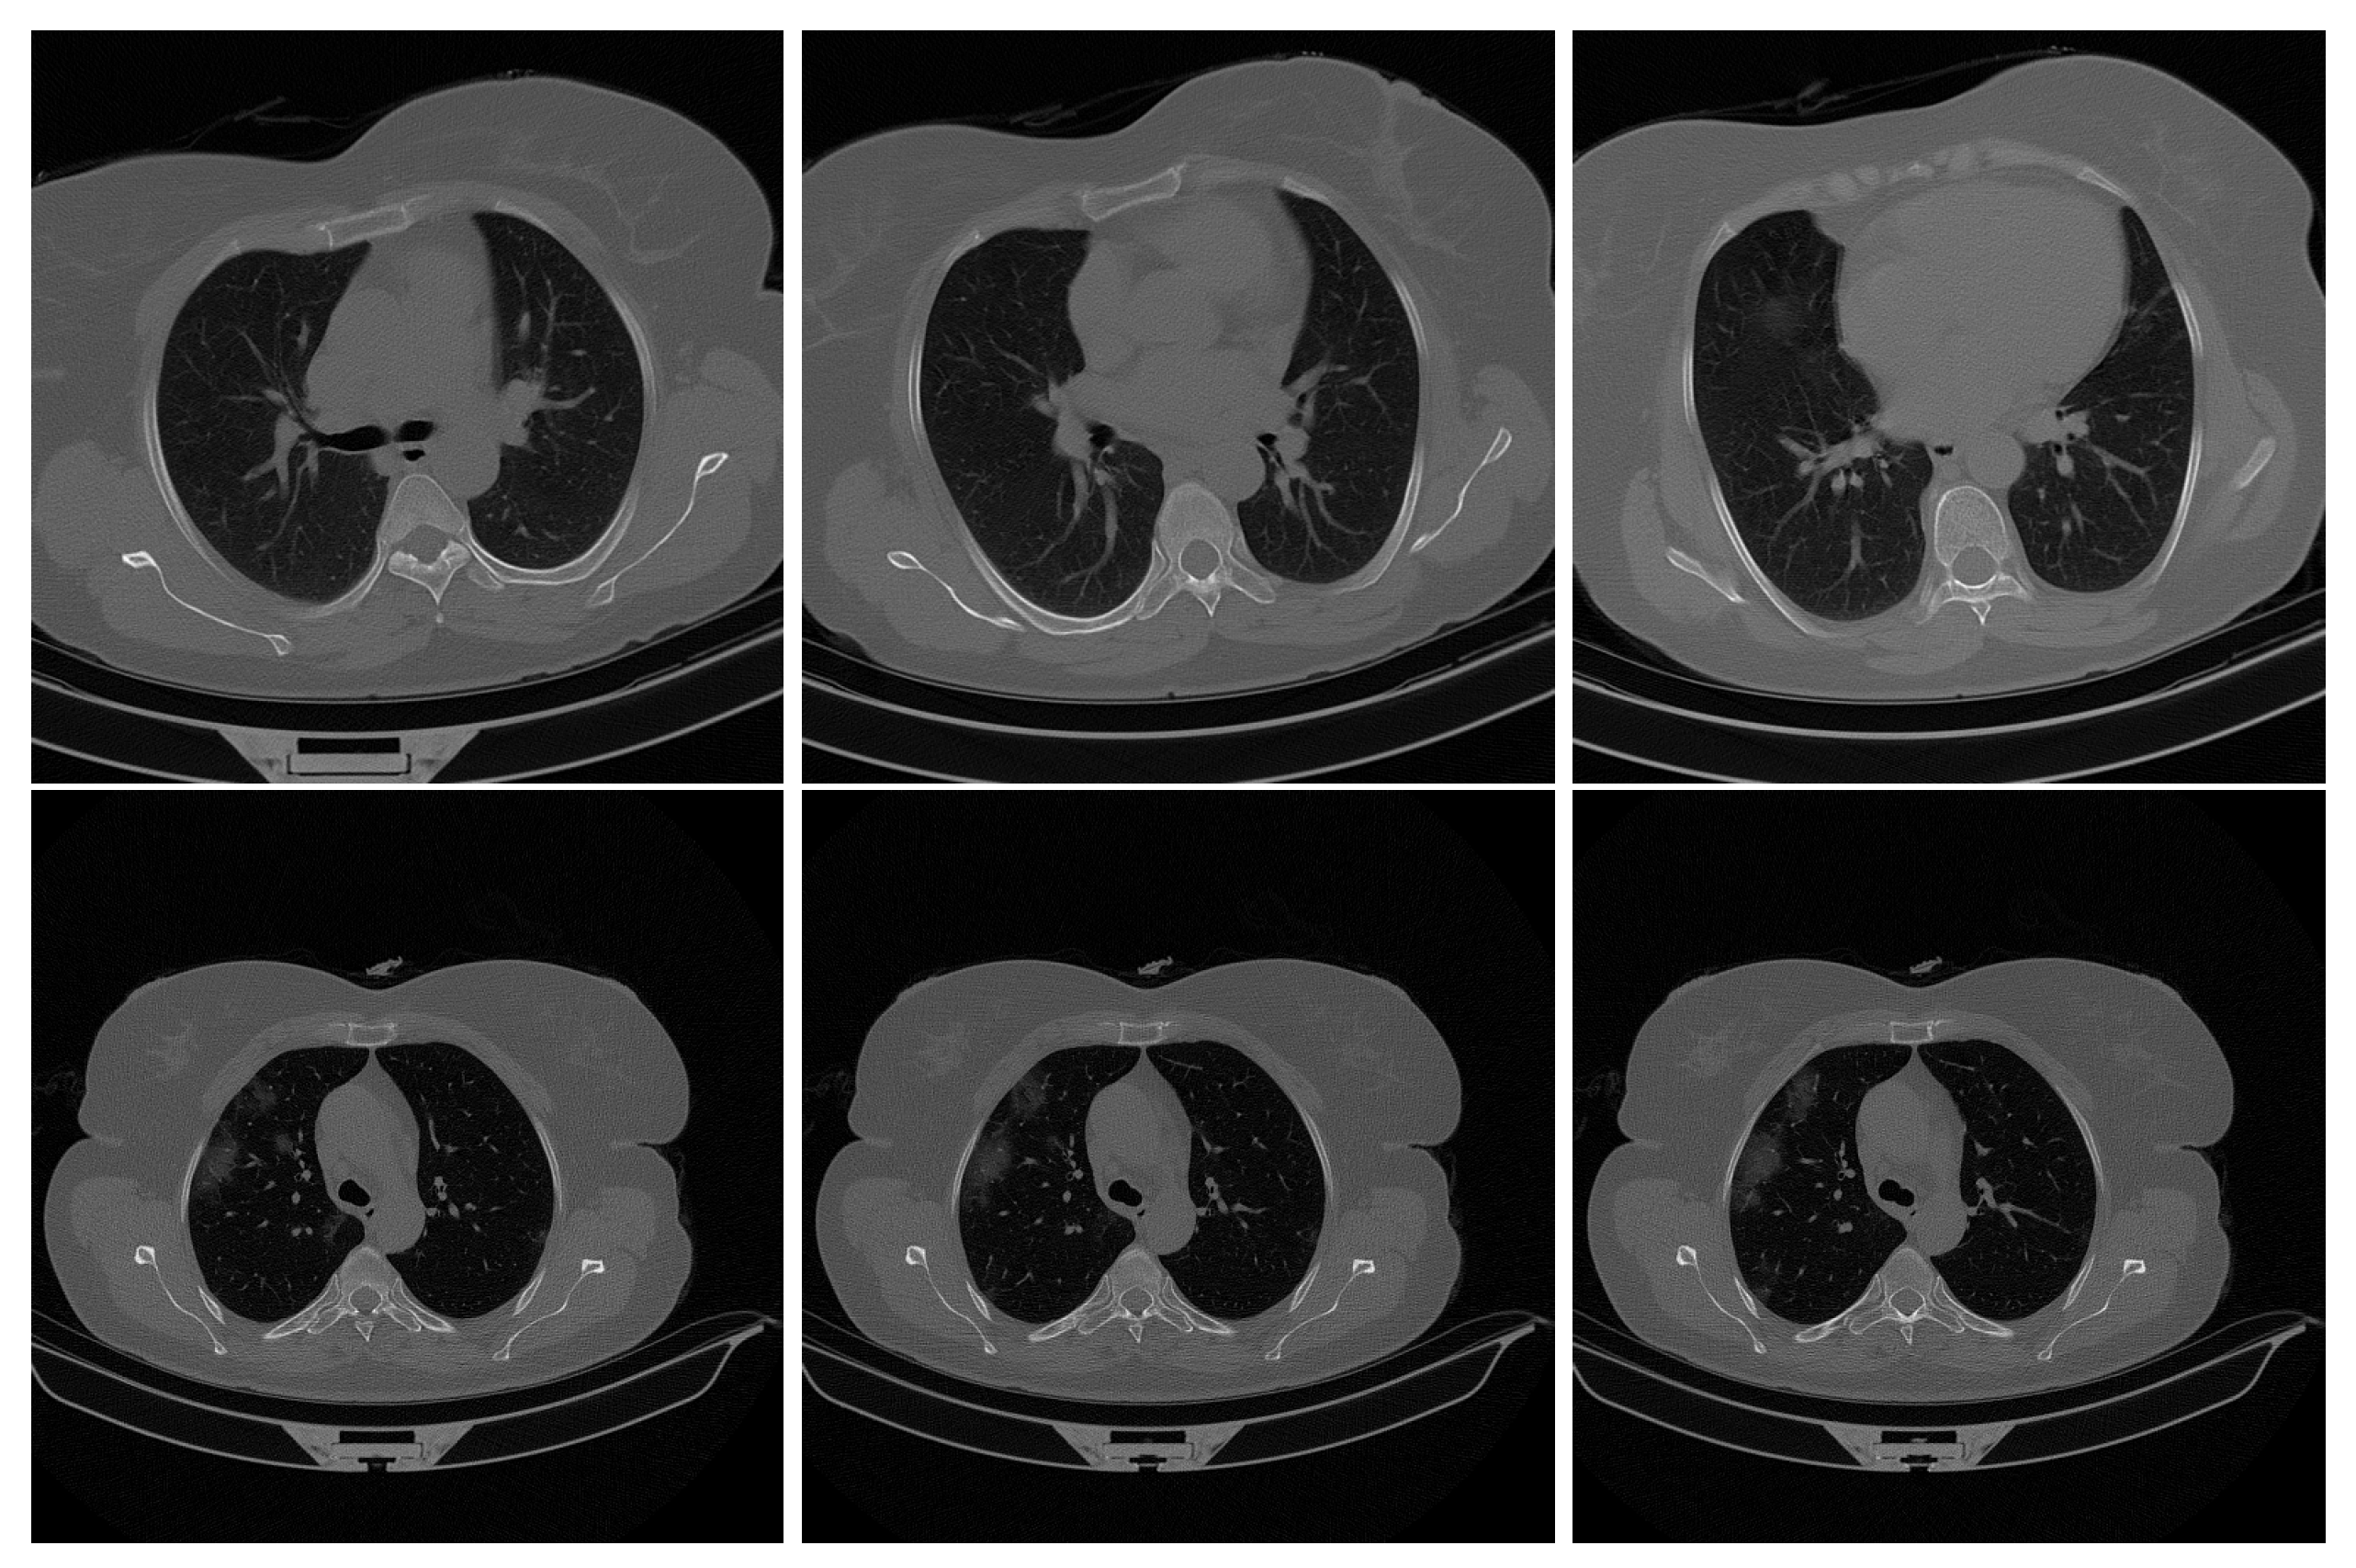

This study collected 7593 COVID-19 images from 466 patients, 6893 normal images from 604 patients, and 2618 CAP (Community-acquired pneumonia) images from 60 patients. For our experiments, we utilized a COVID-19 X-ray lung scan dataset from a study [37] available on Kaggle, which served as our training, validation, and test datasets. The original image size for all images was 512 × 512 pixels, which we resized to 128 × 128 pixels for consistency.

The dataset was categorized into two classifications: COVID and non-COVID. Specifically, we gathered 7593 images from 466 COVID-19-infected patients and 6893 images from 604 normal patients. We had 14,486 images, with a nearly balanced distribution between the two classifications, resulting in a close to 50/50 split. Figure 5 show samples of the dataset.

The X-ray lung scan images were placed into a folder directly which was divided into “COVID” and “non-COVID” folders. Figure 6 below shows the dataset folder structure.

The folder structure was designed to maintain a balanced classification while limiting the data used during model training. We randomly selected 2000 images from each classification and converted the dataset to the “.npy” format to achieve this. Subsequently, we split the dataset into train and test datasets.